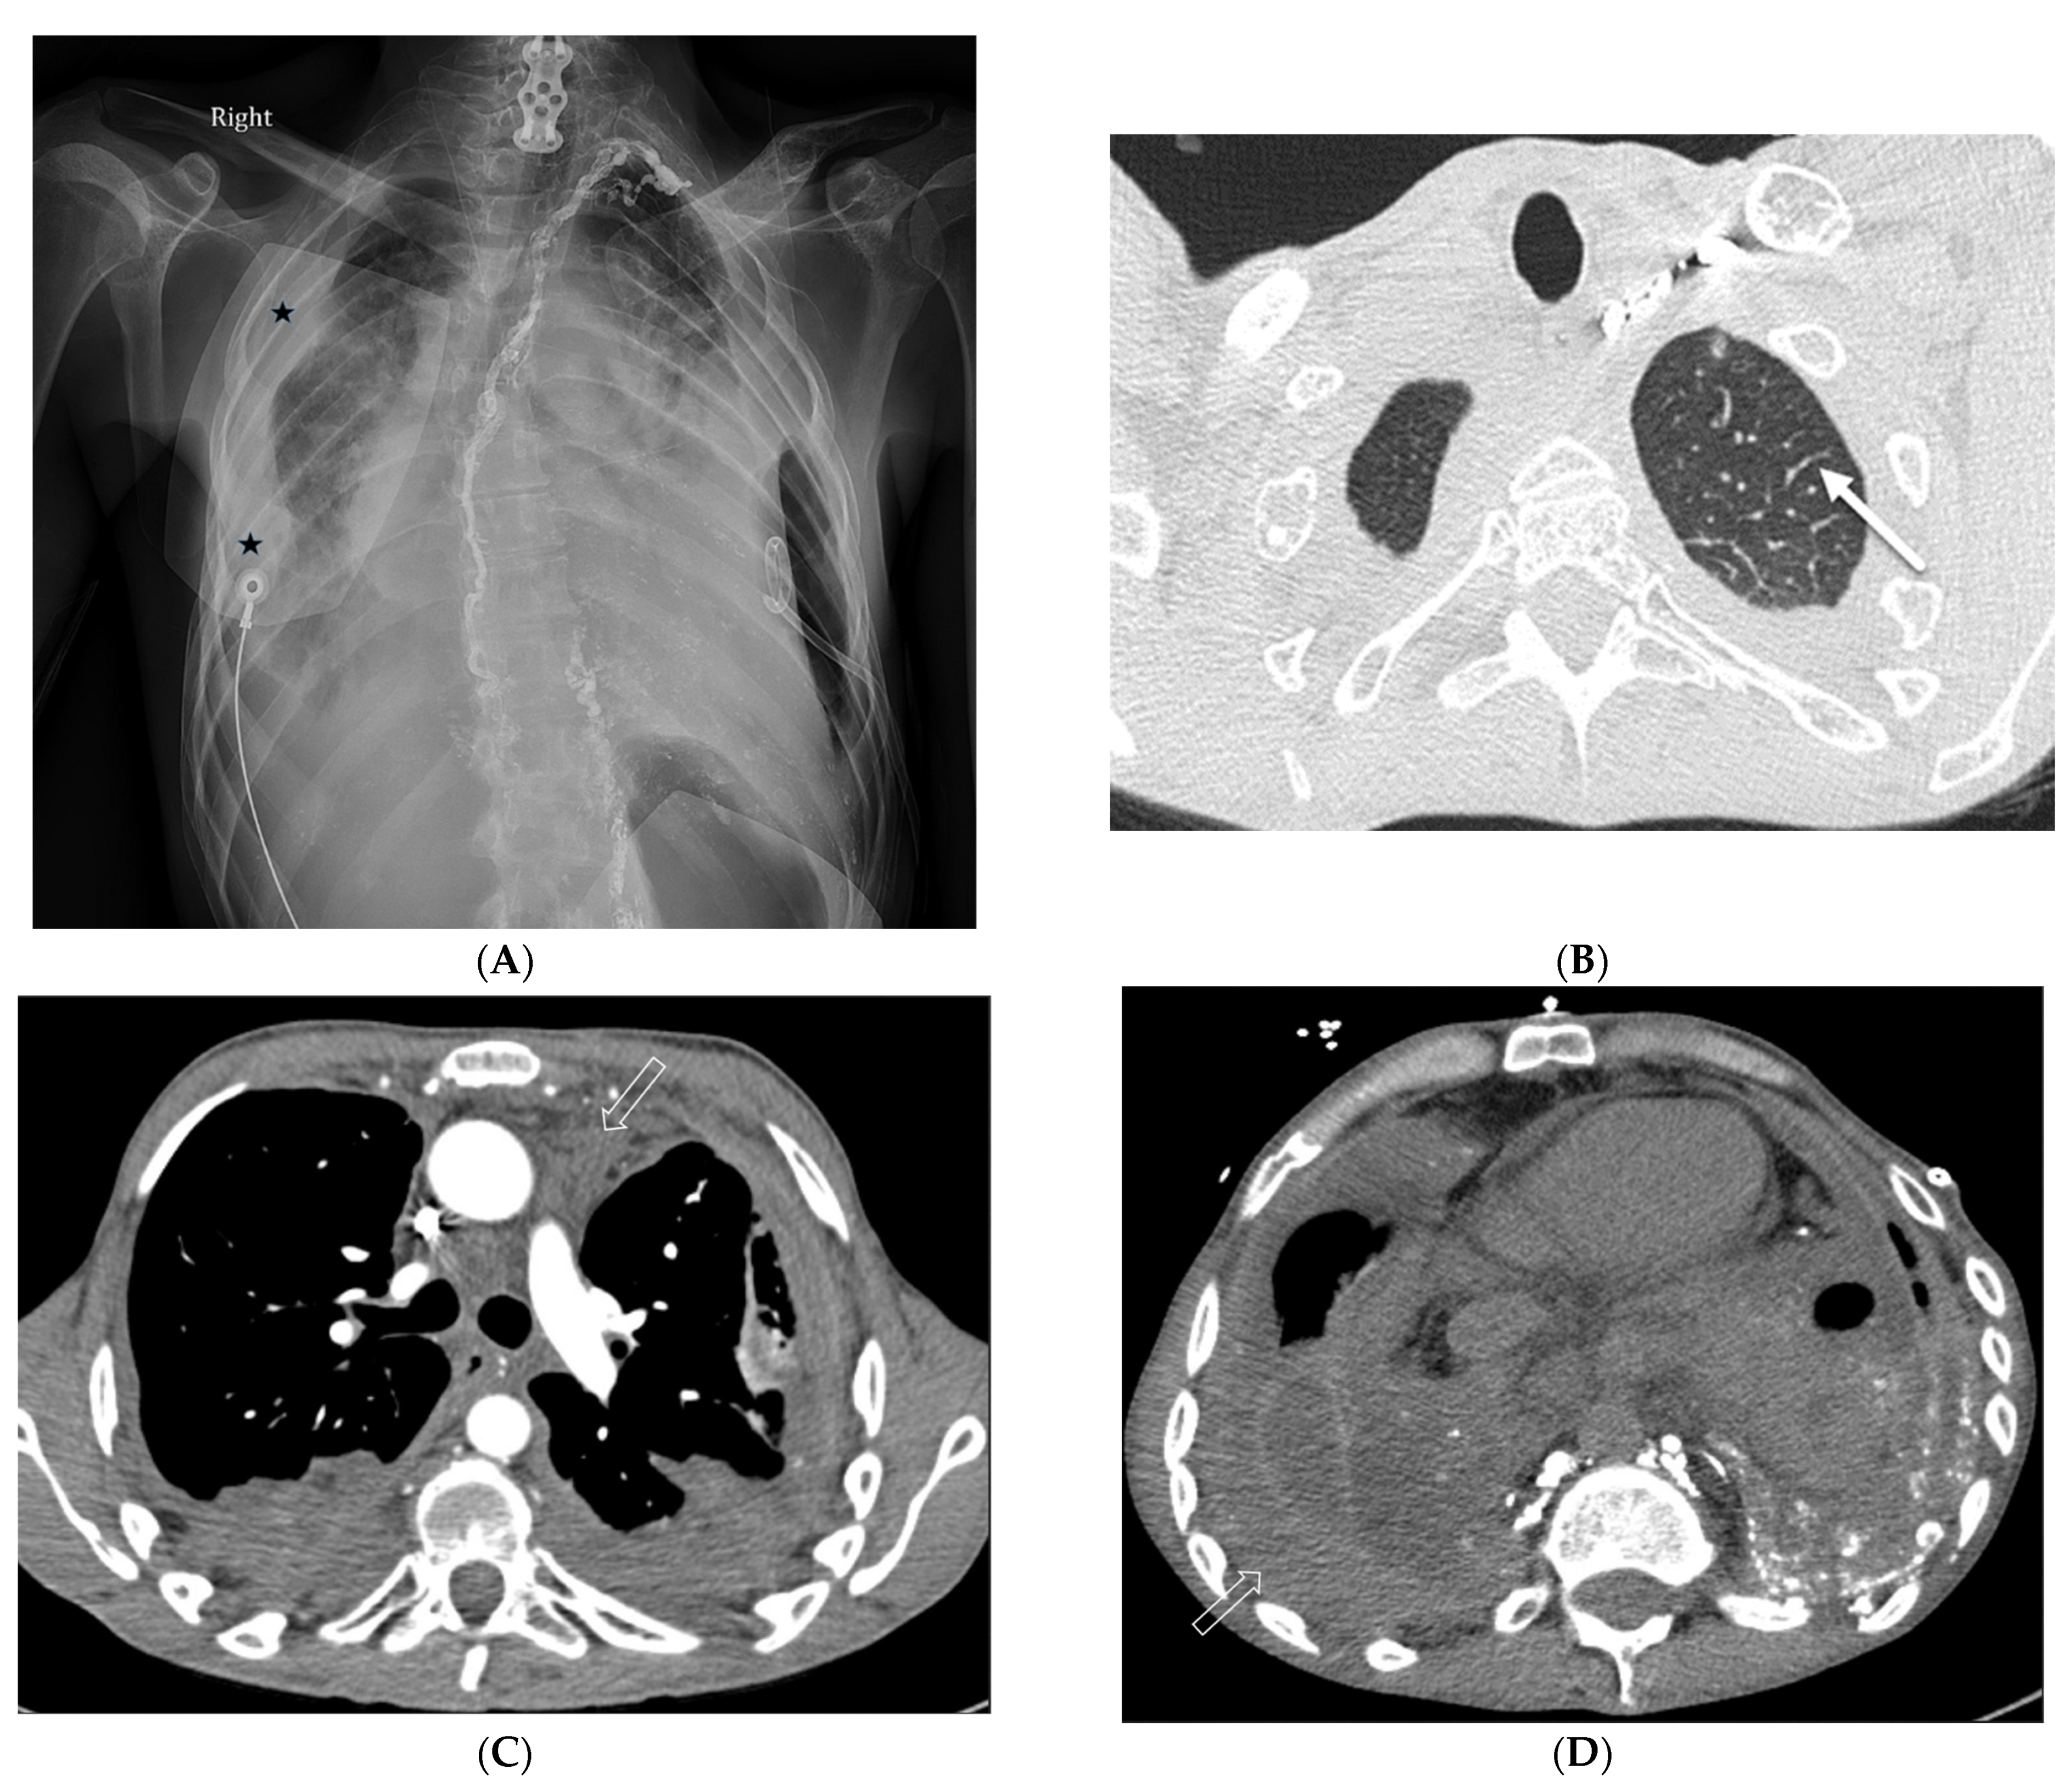

4.7. Pulmonary Vein Stenosis (PVS)

7.3. Diffuse Pulmonary Lymphangiomatosis

7.4. Congenital Pulmonary Lymphangiectasia